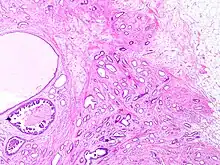

Tubular carcinoma is a subtype of invasive ductal carcinoma of the breast.[2][3] More rarely, tubular carcinomas may arise in the pancreas[4] or kidney.[5] Most tubular carcinomas begin in the milk duct of the breast and spread to healthy tissue around it.[6][7]

Tubular carcinomas are generally around 1 cm. or smaller, and are made up of tubules. They are usually low-grade.[2] Elastosis has been noted as common but is not present in all cases.[11]

- 1 2 Stavros, A. Thomas (2004). Rapp, Cynthia L.; Parker, Steve H. (eds.). Breast Ultrasound. Lippincott Williams & Wilkins. pp. 647–649. ISBN 978-0-397-51624-7. OCLC 1065689596. p. 649:

A highly differentiated invasive carcinoma that forms well-defined tubules (containing epithelium, but no myoepithelium) and that have abundant desmoplastic fibrous stromal reaction between the tubules.